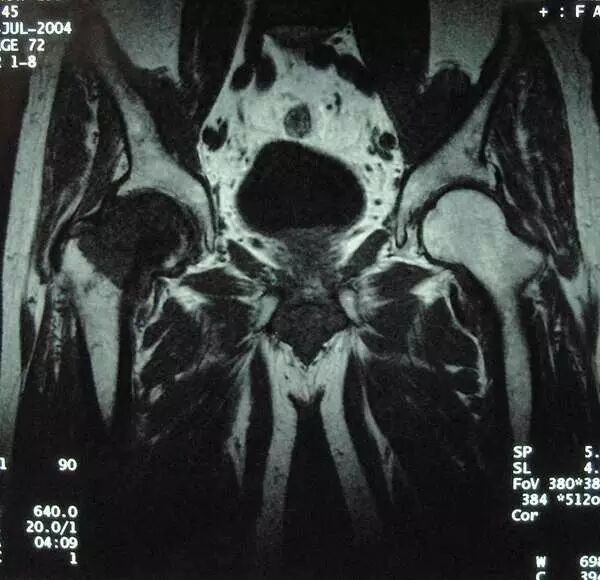

男  60岁 右股骨头颈部透明细胞软骨肉瘤,术前MRI片

在放射学上,透明细胞软骨肉瘤显示为位于长骨的骨骺中的溶解性病变。